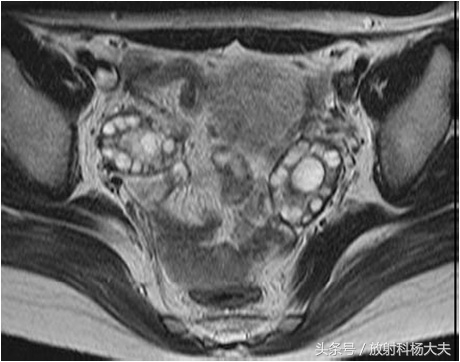

MRI属于无创检查,做过MRI的朋友都知道,患者只需要在那躺着,各项检查就这么神不知鬼不觉的完成了。而且MRI对人体没有任何电离辐射,这点尤其适合那些年轻的或者想生育的女性朋友们。MRI对软策划有极好的分辨率,可以通过多参数成像提供丰富的诊断信息,而且可以通过多角度成像选择各种剖面,获得其他成像技术所不能或难以获得角度的图像。卵巢是位于子宫两侧的一对卵圆形的生殖器官。正常卵巢信号在 T1WI上为均匀的中等或稍低信号强度,内部结构不易分辨。T2WI序列表现为多个大小不一的小圆形或小卵圆形的,均匀高信号囊性结构,囊内信号与液体一致,位于卵巢皮质内,典型呈花环样排列,以T2WI压脂序列显示最清晰。囊壁在 T1WI表现为等信号,T2WI囊壁较T1WI显示清晰,呈均匀的等低信号。在生育年龄妇女,卵巢髓质内含有大量富含血管的疏松结缔策划,T2WI上也表现为稍高信号。正常女性单侧卵巢卵泡数目6~7个,一般不超过10个,正常卵巢体积约6~7 cm3大小。在排卵期,优势卵泡的直径最大可达2 cm。多囊卵巢综合症患者的卵巢 MRI信号与正常卵巢一致,而卵巢体积较正常卵巢增大,卵泡数目较正常增多,卵泡排列无特别规律,可沿周边分布,亦可弥漫分布。与正常女性相比,多囊卵巢综合症患者双侧卵巢较正常卵巢增大2~3倍,卵巢内可见许多闭锁卵泡和处于不同发育期的卵泡,但无成熟卵泡生成及排卵迹象。